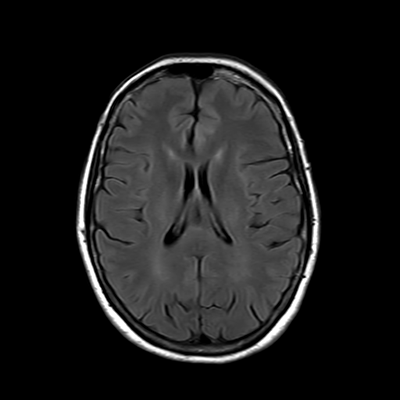

You also obtain an MRI of his brain once it's clinically safe to do so.

MRI brain (FLAIR)

You are now very concerned that he truly has an infectious meningoencephalitis.